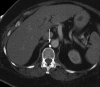

Chylous leaks, such as chylothorax and chylopericardium, are uncommon effusions resulting from the leakage of intestinal lymphatic fluid from the thoracic duct (TD) and its tributaries, or intestinal lymphatic ducts. The cause can be either traumatic (thoracic surgery) or nontraumatic (idiopathic, malignancy). Treatment has traditionally consisted of dietary modification (nonfat diet) and/or surgery (TD ligation, pleurodesis). Thoracic duct embolization (TDE) has become a viable treatment alternative due to it high success rate and minimal complications. In this article, the authors describe the etiologies of chylothorax, patient population, outcomes, and long-term follow-up of TDE patients. Relevant lymphatic anatomy and physiology are reviewed, with special attention paid to the formation of the duct by tributaries at the cisterna chyli (CC). The technique of TDE is outlined, including bilateral pedal lymphangiography, TD cannulation, and embolic agents used for the procedure.